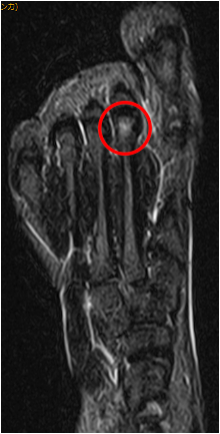

MRI画像による診断

レントゲンでは軟骨などがはっきりと描写できないため、

MRIを撮影します。

左のMRI画像では、StageⅡの画像です。

左のMRI画像は足を上側から見ているものです。

右側のMRI画像は足を輪切りにして見ているものです。

赤矢印で示した第3中足骨頭には輝度変化が見られます。

このように輝度変化が見られる原因は、栄養障害が起こっているからです。